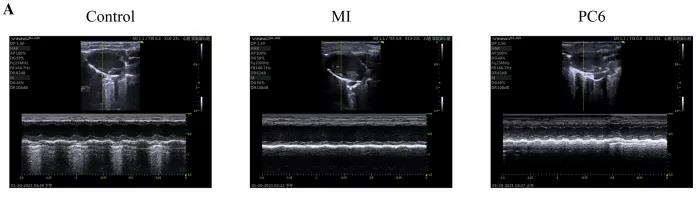

為了探討針刺PC6穴對(duì)心肌損傷的影響,作者首先評(píng)估了心功能和梗死面積。超聲心動(dòng)圖結(jié)果顯示MI組的EF(ejection fraction)和FS(fractional shortening)均較對(duì)照組明顯降低。PC6穴位治療后,EF和FS均增加。針刺治療5天后, 采用TTC染色檢測梗死面積。結(jié)果顯示,針刺治療顯著減小心肌損傷的大小。采用ELISA法測定反映急性心肌損傷的心肌特異性血清酶,包括心肌肌鈣蛋白T (cTnT)和心肌肌鈣蛋白I (cTnI)的水平。結(jié)果表明,心肌梗死術(shù)后cTnT和cTnI水平升高,針刺可顯著降低血清酶水平。